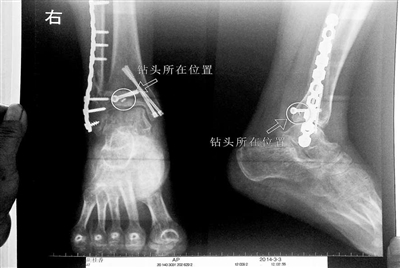

胡女士的腿部X光圖

看著X光片中自己腿內(nèi)的異物,胡女士就感到莫名的擔(dān)憂。胡女士于2013年3月在北京市豐臺區(qū)右安門醫(yī)院進(jìn)行了一次骨折手術(shù),術(shù)后醫(yī)生才發(fā)現(xiàn)手術(shù)時用來打眼用的鉆頭不慎遺留在了胡女士的骨頭中,并且無法取出。

近日,在豐臺區(qū)右安門醫(yī)院,北京青年報(bào)記者見到了胡女士,她走起路來顯得一瘸一拐,腿腳并不利索。在她帶來的X光片上,可以清晰地看到,有一個異物存在于腿內(nèi)部。

“我當(dāng)時就嚇蒙了,怎么會有一個鉆頭在骨頭里?”胡女士余悸未消地說,第二天拍攝的X光片顯示,2厘米左右的鉆頭遺留在她右腳腳踝上部的骨頭內(nèi)。

胡女士說,當(dāng)時旁邊的醫(yī)生勸慰自己,稱鉆頭留在腿里并不會有什么問題。出院后,胡女士每個月都會來醫(yī)院做復(fù)查,拍X光片。她說,每次都能夠清晰地看見自己骨頭里的那個明晃晃的“小東西”。